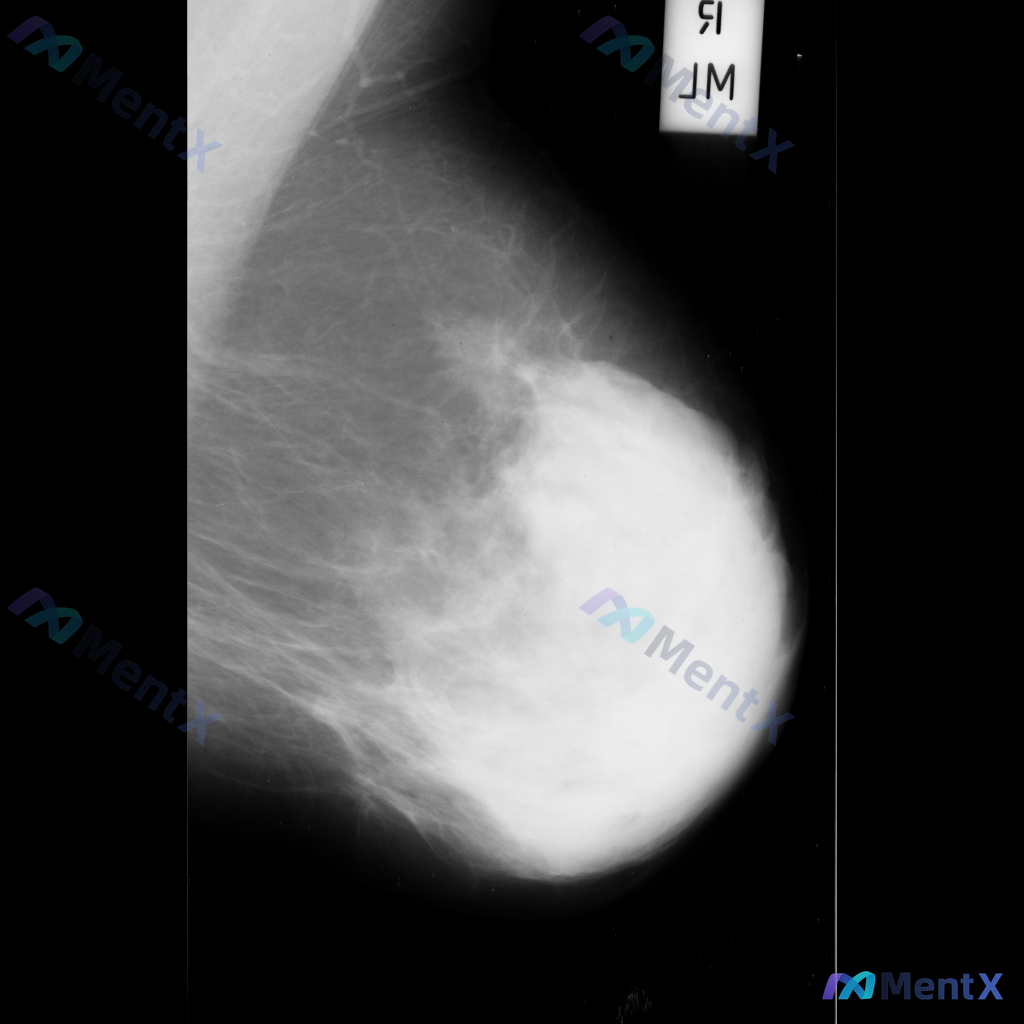

整理到一张乳腺钼靶影像的描述资料,想请大家帮忙看看更倾向哪种情况。 【基本影像背景】 - 检查侧:右侧乳腺 - 乳腺构成:不均匀致密型(BI-RADS C型) 【影像异常发现】 - 右侧乳腺见一处不规则形高密度肿块 - 肿块边缘呈毛刺状或星芒状 - 局部伴有显著的结构扭曲 - 无明确钙化灶显示 -...

整理到一张乳腺钼靶影像资料,可见一处明确的异常表现: - 局部有形态不规则的占位性病灶,密度高于周围正常腺体组织 - 病灶边缘有细小的放射状结构向周围延伸 - 病灶周围的乳腺腺体和纤维组织结构排列紊乱 另外,该病例的乳腺组织整体密度较高(不均匀致密型)。 想和大家讨论:对于这张影像的异常表现,用哪些...